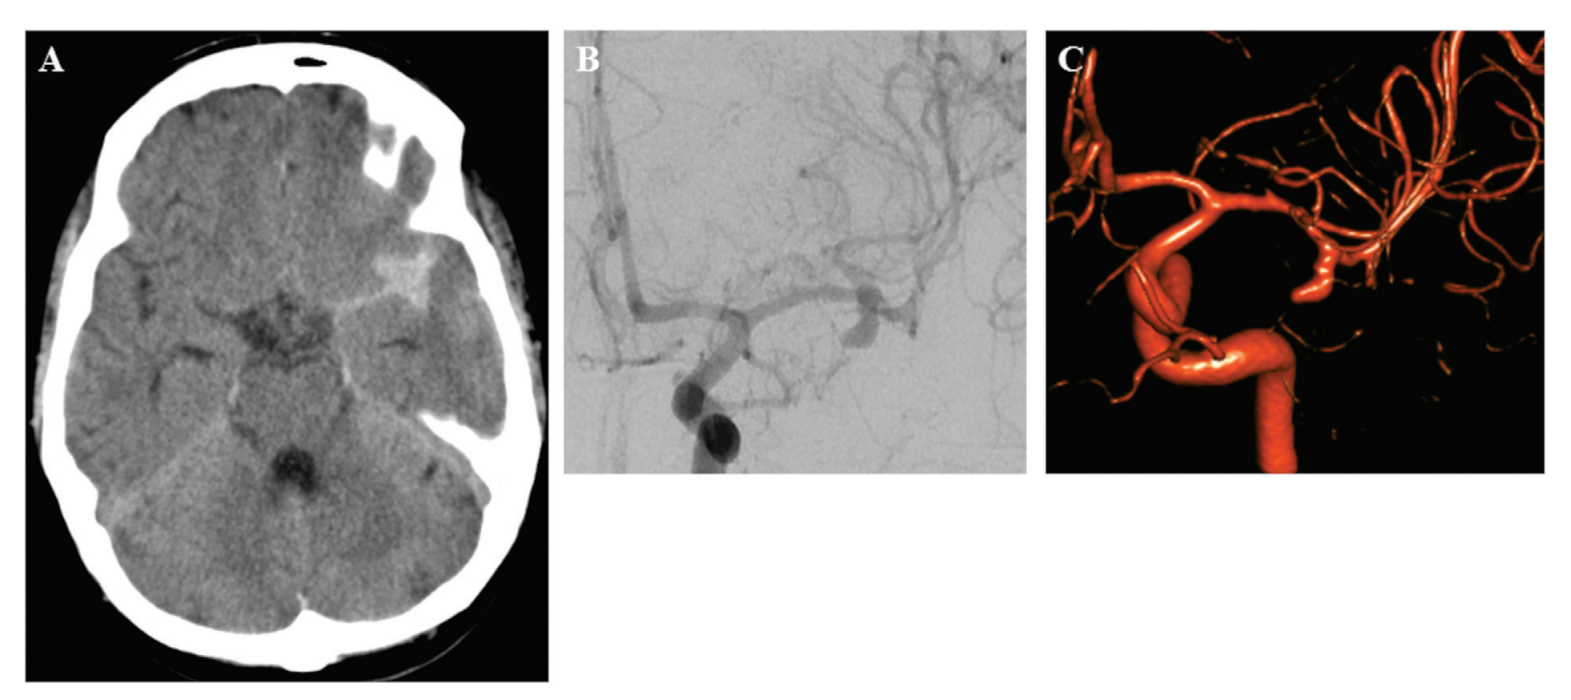

图3:术前CT(A)显示左侧外侧裂蛛网膜下腔出血;(B)正位DSA和(C) DSA三维重建显示左侧大脑中动脉M2段动脉瘤。